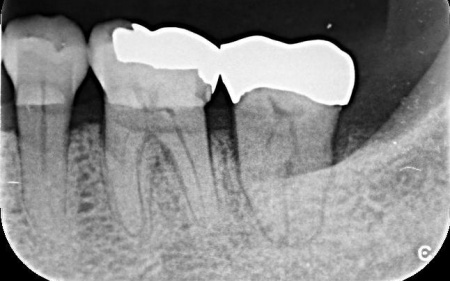

確認したところ、右上奥歯(第2小臼歯/5番)のプラスチックの詰め物が欠けていました。

プラスチックの詰め物は強度が低く、劣化しやすいといった特徴があります。患者様は噛み合わせの力が強く、詰め物に過度な負担がかかったことが破損の原因と考えられました。